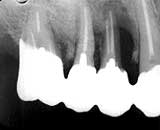

【症例1】(図14-18)は65歳・男性の654| 部位にFOpと、連続波 Nd/YAG LASER による根面処理を行った症例です。術前の抜髄時の所見 では、5|遠心側に多量の歯肉縁下歯石と 根尖側1/4におよぶ歯槽骨破壊が観察されます。

5|遠心側では、抜歯窩の骨再生と同様に 術後1年ほどの間に周囲歯槽骨の存在する高さに比例した歯槽骨再生が認められます。 6|の遠心側でも同様に歯槽骨再生が認めら れますが、周囲歯槽骨の骨稜が低いために著明な回復は認められません。

図14.初診時Dental写真

患者:65歳、男性

図15.術後3か月

(FOp+レーザー根面処理)

図16.術後6か月

破壊骨面の平坦化が認められる

図17.術後1年

骨再生はおおむね終了

図18.術後5年

メインテナンスが悪いと術後2年を境に

再び吸収が進行することもある